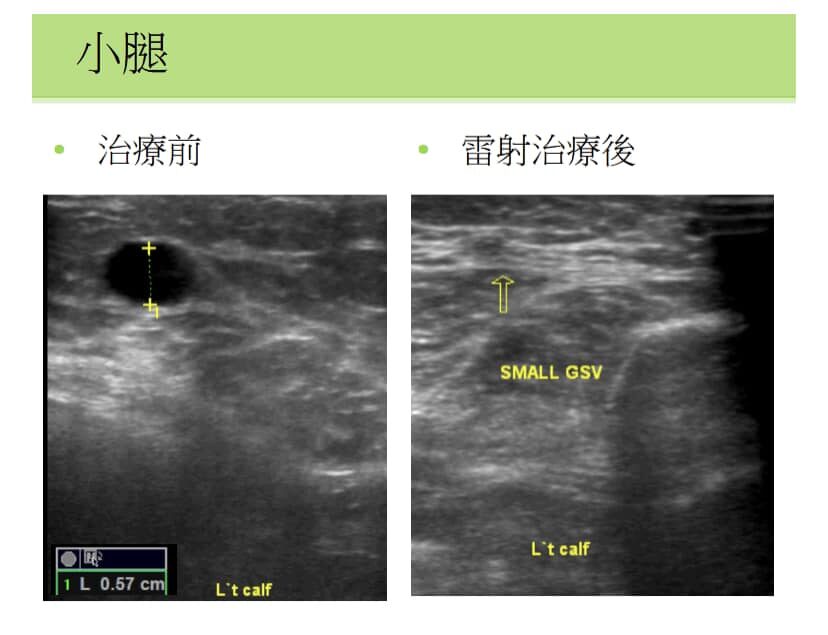

靜脈雷射美容治療是一種非侵入性的皮膚表層雷射技術,主要用來改善蜘蛛靜脈、毛細血管擴張與淺層血管病變。透過雷射能量精準照射異常血管,使其受熱凝固、崩解,最終被身體自然吸收。

此療法不需打針或開刀,多用於治療臉部或腿部的細小紅色、藍色血絲,屬於美容性質的治療,效果明顯且恢復期短。